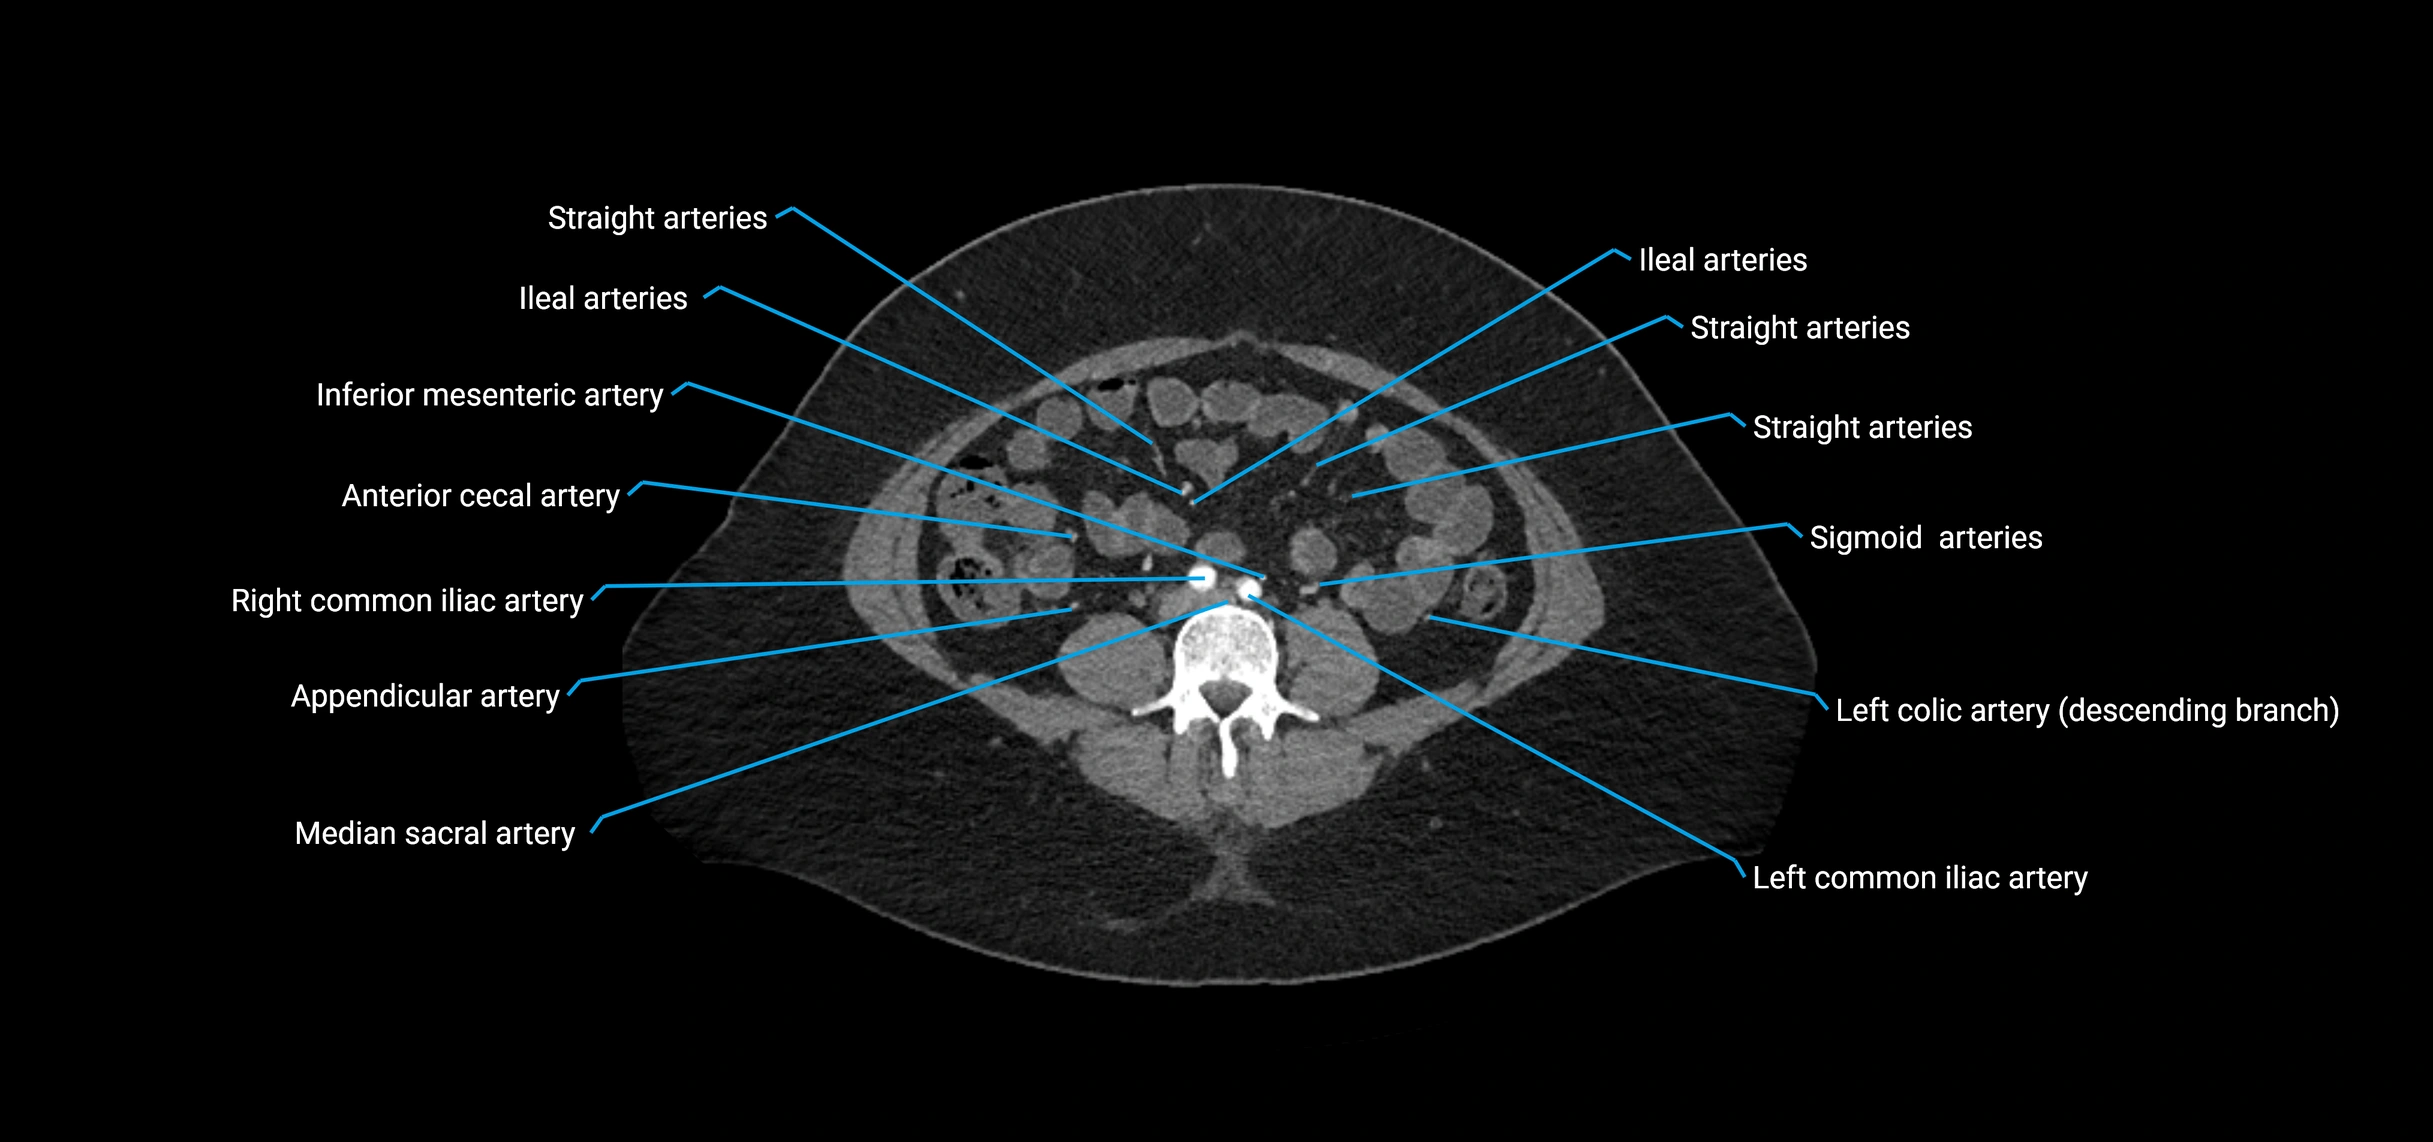

CT Appearance

Non-contrast CT:

• Appears as a tubular soft tissue structure anterior to vertebral bodies

• Calcified atherosclerotic plaques appear as hyperdense foci along the wall

• Useful for screening abdominal aortic aneurysm (AAA) size and mural calcification

Contrast-enhanced CT (CTA):

• Gold standard for abdominal aortic imaging

• Provides excellent detail of lumen, wall, aneurysm, thrombus, and branch vessels

• Multiplanar and 3D reconstructions help in aneurysm measurement, stent graft planning, and dissection evaluation

• Detects acute rupture, traumatic injury, or occlusion with high sensitivity